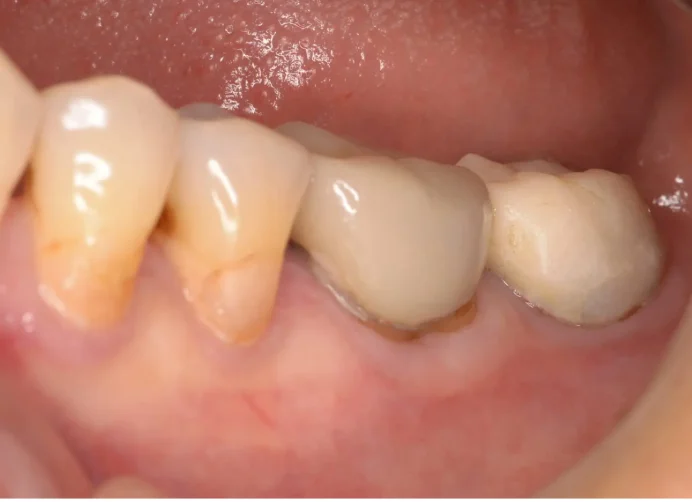

Before

After

セラミック治療により見た目と歯茎の炎症を改善(40代女性)

5回 / 総額115,000円リスク・副作用:歯軋りが強い場合破損する場合がある 歯の神経が生きている場合一時的にしみることがある